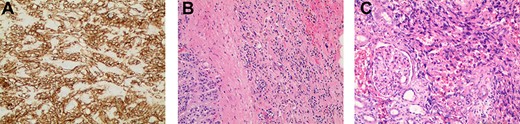

Appearance of effusion in the left retroperitoneal space in transverse (left) and coronal (right) planes on CT; it can be seen encroaching on the spleen; subsequent cytology ruled of malignant effusion.

Two weeks post-resection, the patient was recovering as expected. At 4 weeks post-resection, radiation oncology recommended 7 weeks of intensity-modulated radiation therapy to both the surgical site and at-risk nodes identified on CT. Six weeks post-resection, the patient presented to the ED with nausea and vomiting. Abdominal CT revealed a retroperitoneal effusion at the surgical site (Fig. 3). At this admission, the patient also tested positive for COVID-19, delaying drain placement and his radiation treatments for 2 weeks.